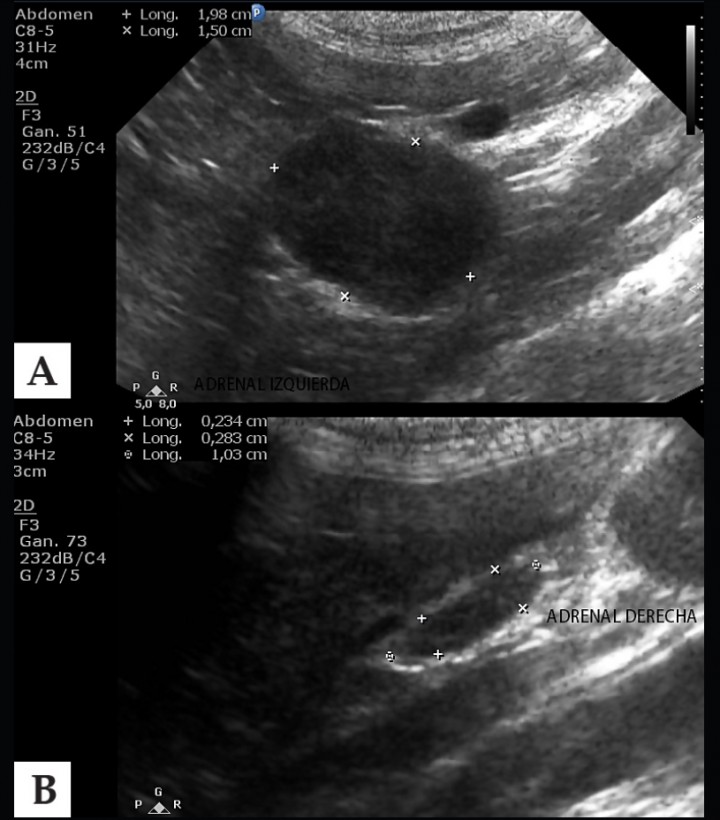

Las pruebas de diagnóstico por imagen, tales como la ecografía son fundamentales en el diagnóstico del HAP ya que permiten valorar la presencia de masas adrenales. En el presente caso clínico, se visualizó mediante ecografía abdominal, la presencia de una masa en la glándula adrenal izquierda de 1,98 por 1,5 cm de diámetro (Fig. 2). Otras técnicas de diagnóstico por imagen como la tomografía computarizada y la resonancia magnética pueden ayudarnos a definir de forma más precisa la extensión de la masa, así como la invasión o ausencia de la misma de la vena cava caudal.[ Schulman RL. Feline primary hyperaldosteronism. Vet Clin North Am Small Anim Pract 2010; 40:353-9. [PubMed] ] Se confirmó el diagnóstico de HAP por la sintomatología clínica que presentaba el animal, la hipokalemia, la hipertensión sistémica, el aumento de los valores de aldosterona y la visualización de una masa adrenal mediante ecografía.

<p>A: Imagen ecográfica de la glándula adrenal izquierda que refleja aumento de tamaño con aspecto neoplásico. B: Imagen ecográfica de la adrenal derecha de tamaño y aspecto normal.</p>

A: Imagen ecográfica de la glándula adrenal izquierda que refleja aumento de tamaño con aspecto neoplásico. B: Imagen ecográfica de la adrenal derecha de tamaño y aspecto normal.